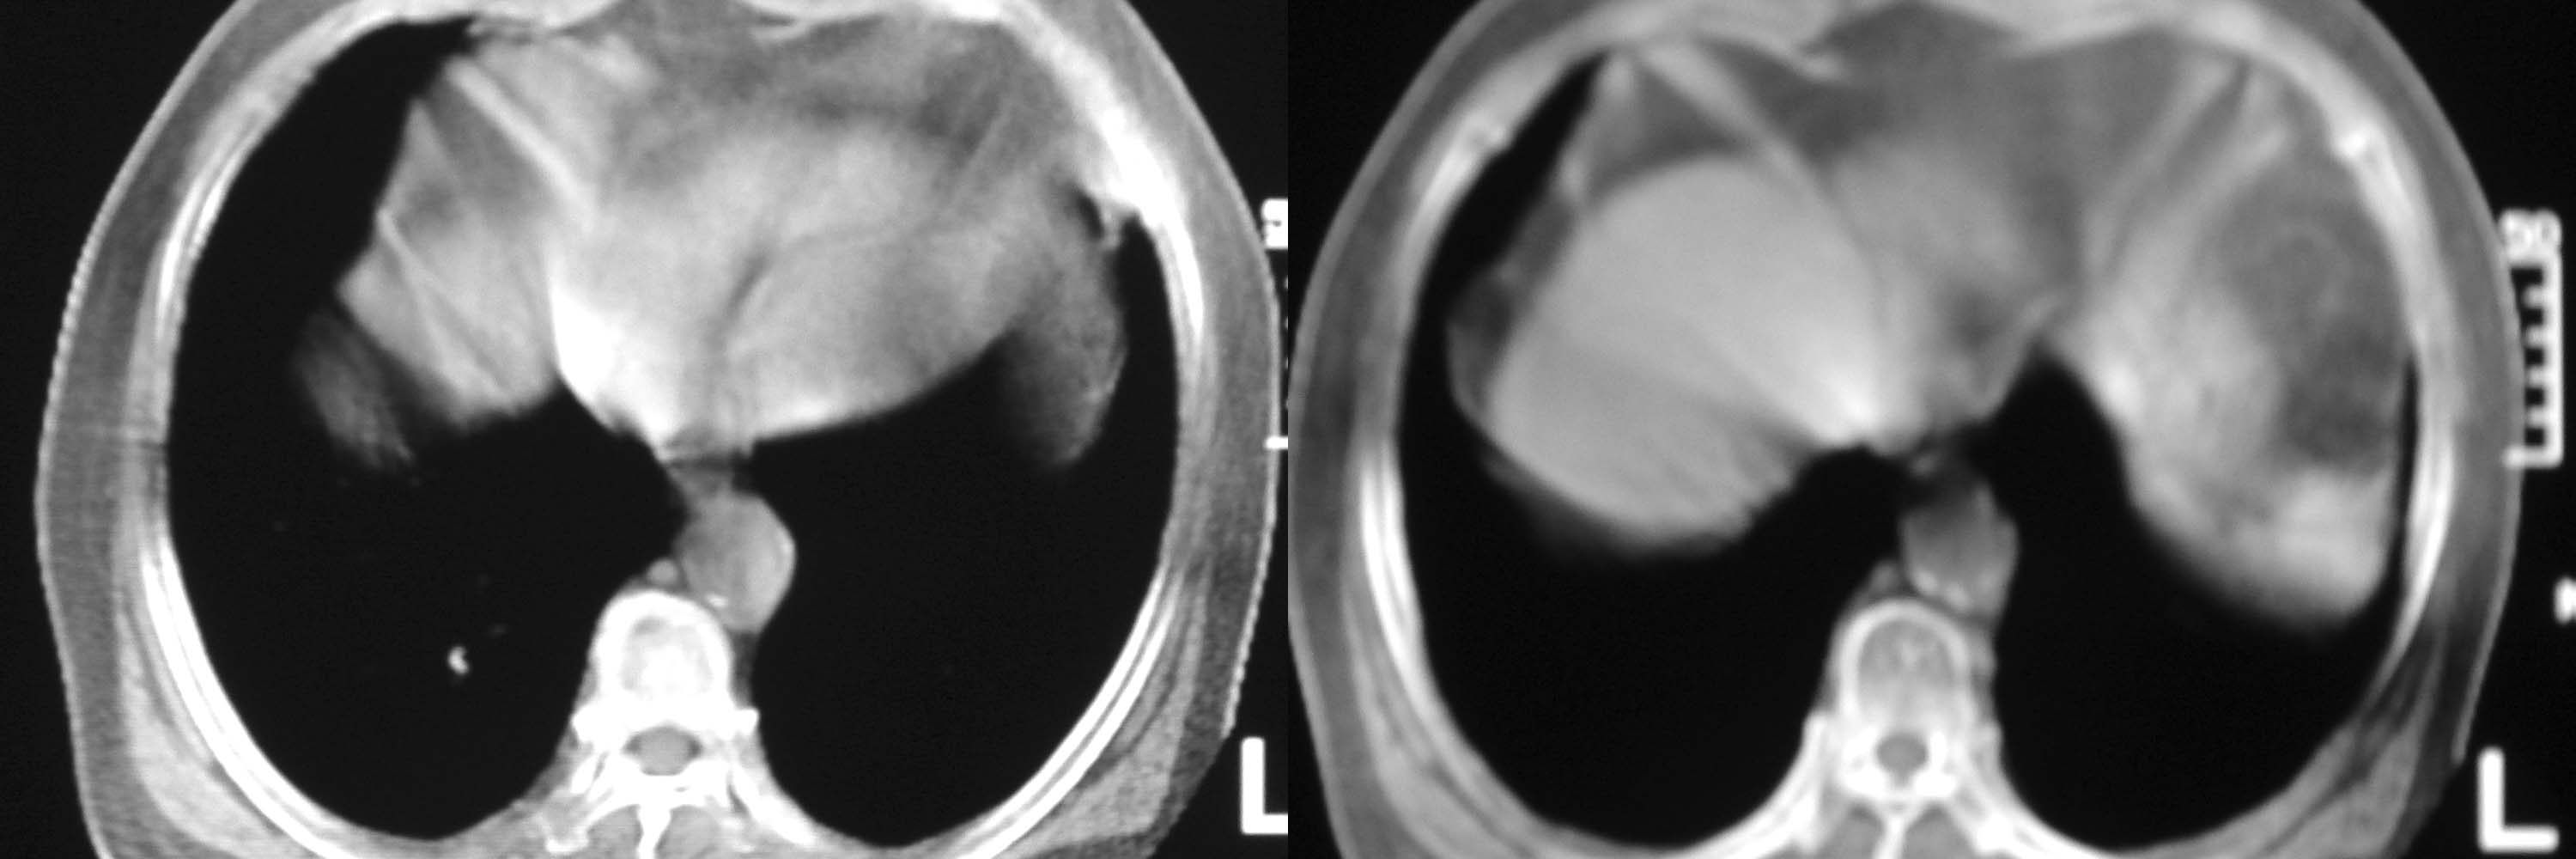

女78岁咳嗽咳痰无咳血平片报右上肺不张、慢支、肺气肿、请老师们帮忙看看,箭头所指是什么?是占位吗?有肺气肿吗?谢谢

箭头所指考虑血管影;纵隔内及双肺门区多发淋巴结钙化;不支持肺气肿。

箭头所指考虑血管影(头臂血管);纵隔内及双肺门区多发淋巴结钙化;不支持肺气肿。